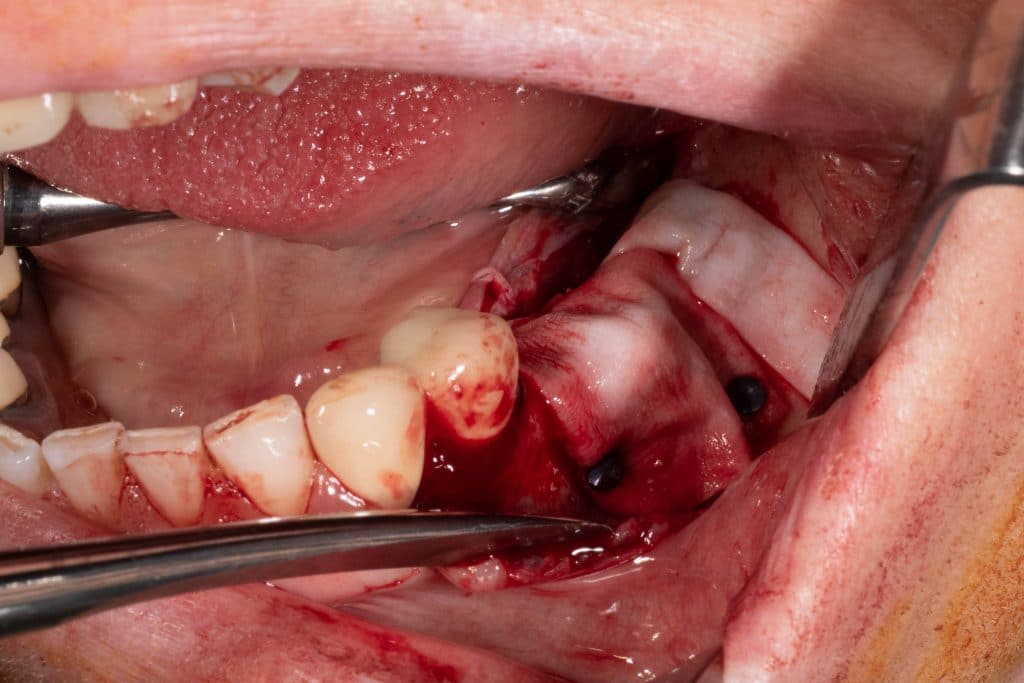

Removal of 2 broken implants with piezoelectric instrument

Implant placement in a correct prosthetic position